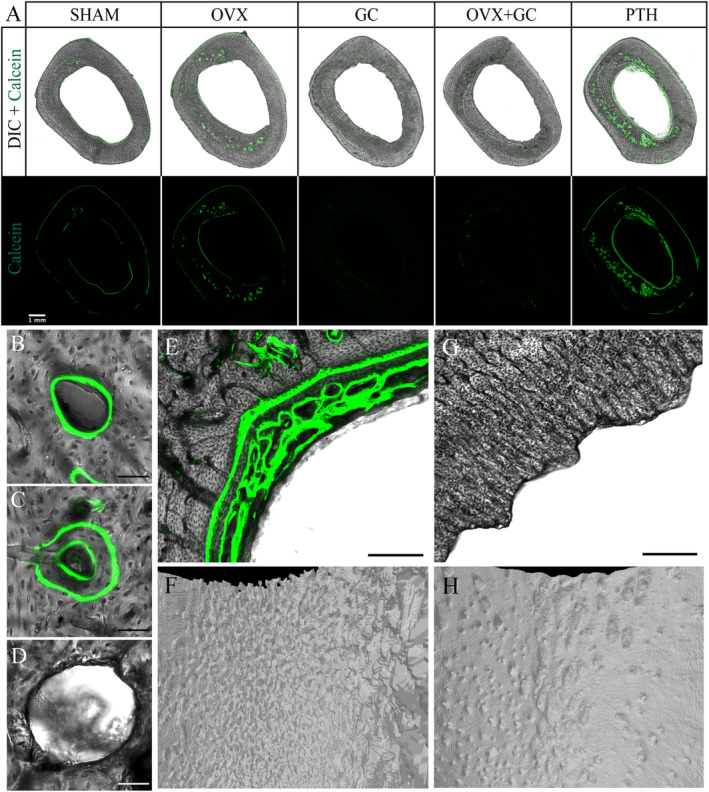

Fig 4.

(A) Differential interference contrast (DIC) and fluorescent confocal microscopy images of transverse sections of rabbit tibiae in various treatment groups. Green fluorescent signal from calcein depicts areas of active bone formation. Absent signals from GC‐treated rabbits are due to inhibition of osteoblastic‐mediated bone formation by GC treatment. Scale bar = 1 mm. SHAM = control; OVX = ovariectomy; GC = glucocorticoid; OVX + GC = ovariectomy and glucocorticoid; PTH = parathyroid hormone. (B–D) Representative confocal microscopy images of (B) single‐labeled osteon, (C) double‐labeled osteon, and (D) resorption cavity. Scale bar = 50 μm. (E) Confocal microscopy image of PTH endosteal surface in transverse section. Note the trabecularized appearance of bone formed on the endosteal surface, a feature typical of woven bone. Scale bar = 150 μm. (F) Corresponding three‐dimensional reconstructed micro‐CT image of PTH endosteal surface. (G) Confocal microscopy image of GC endosteal surface in transverse section. Note scalloped appearance of endosteal bone. Scale bar = 150 μm. (H) Corresponding three‐dimensional reconstructed micro‐CT image of GC endosteal surface.

Cortical bone histomorphometry

The calcein labels revealed active bone formation on the periosteal and endosteal surfaces as well as intracortical bone formation within actively forming osteons (Figs. 4 and 6, Table 4). Formation was most pronounced in the PTH group, particularly at the endosteal surface and intracortically (reflected qualitatively in many geometry parameters in Fig. 5). Conversely, the GC and OVX + GC groups exhibited reduced evidence of labeled bone formation on all surfaces (Fig. 4A ). Because of the lack of formation, measures relying upon calcein labels were not assessable for GC and OVX + GC and were reported as no data (ND) in Table 4. Bone formation at both surfaces, Es.MS/BS and Ps.MS/BS, was increased in the PTH group (CIs excluding zero; adj. p < 0.001 and 0.040, respectively). Endosteal bone formation in PTH had a distinct pattern that included well‐organized lamellar bone in places but also disorganized plates with a crude trabecular‐like pattern reminiscent of woven bone in others (Fig. 4E, F ). Ps.MS/BS was highly variable with large outliers detected for SHAM and OVX.